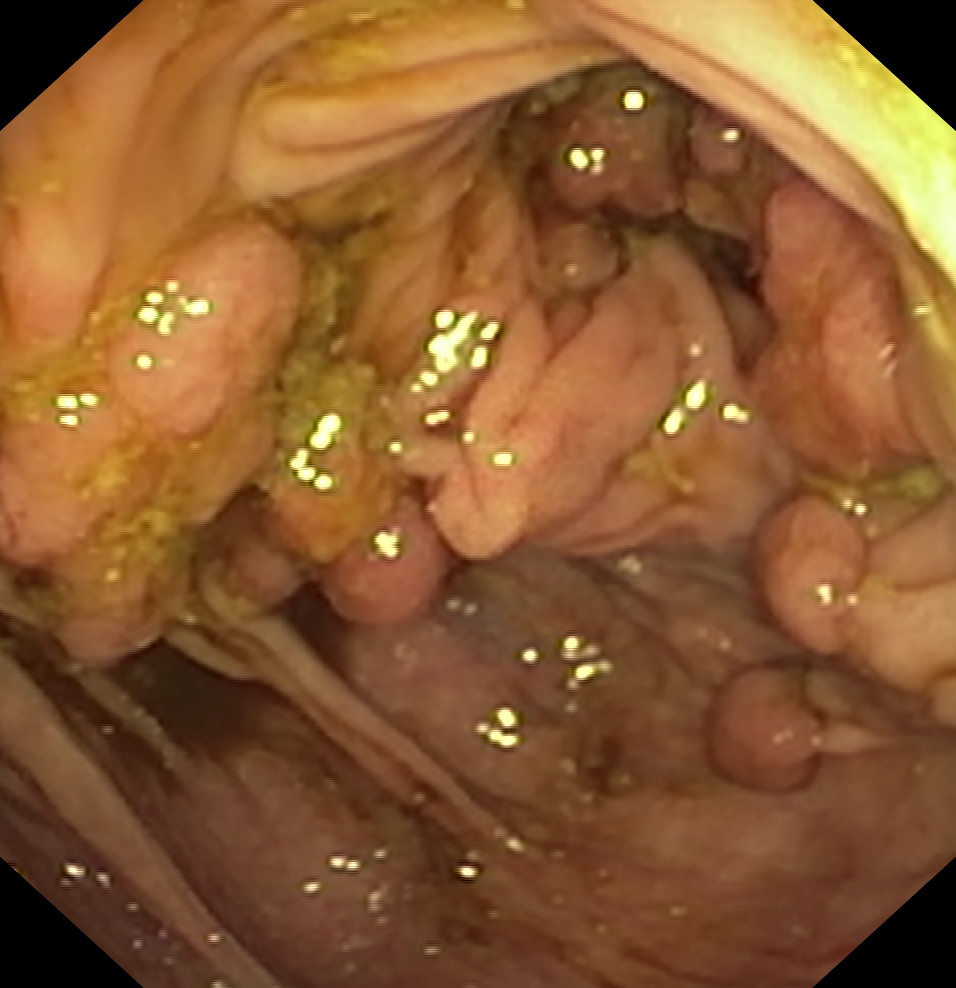

Nowotwory przewodu pokarmowego